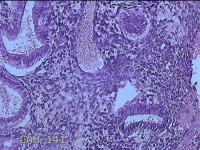

子宫腔赘生物

性别

女

年龄

33岁

临床诊断

子宫内膜息肉?子宫异常出血

一般病史

阴道流血12天。

标本名称

大体所见

灰白粉红色不规则肿物1.5x1.3x0.2cm一堆,表面糜烂。

图2